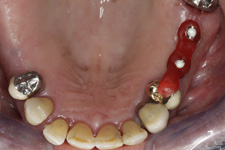

- Velká mezera

Velká mezera

V případě chybění většího počtu zubů v postranních úsecích čelistí je možné ošetření pomocí implantátů, které nahradí ošetření pomocí snímacích náhrad kotvených na zbývajících zubech nebo patře.

Podmínkou je opět dostatečné množství kosti.

Protetické řešení může být pomocí můstku, který je kotvený na implantátech nebo pomocí jednotlivých korunek na implantátech.

V zásadě je možné do těchto můstků zařadit i přirozené zuby, zejména pokud je potřeba tyto zuby ošetřit proteticky - korunkami. Korunky nebo můstky mohou být na implantáty nacementovány nebo přišroubovány.

Zdravé zuby zůstanou zachovány a přitom náhrady jsou pevné, jako na vlastních zubech